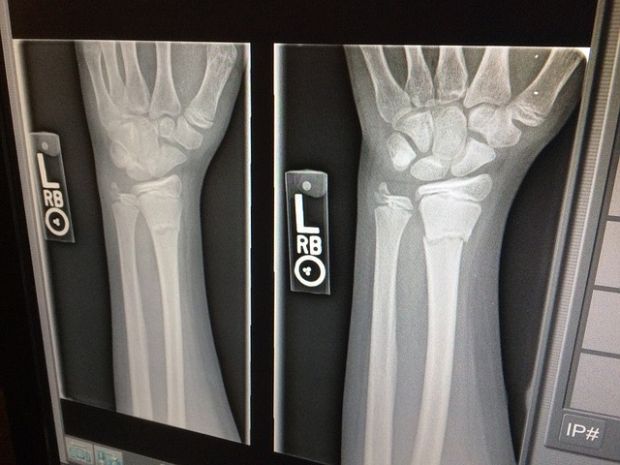

Upravo nedostatak tih enzima otežava tijelu dolazak do kalcija i fosfora iz mlijeka, a oni su zaslužni za jačanje strukture kostiju. Države s najvećom stopom potrošnje mliječnih proizvoda (poput SAD-a i zemala EU) imaju najvišu stopu oboljelih od osteoporoze (gubitak koštane mase).

Također, dok mlijeko prolazi kroz postupak pasterizacije, ono postaje kisela hrana što smeta tijelu pri održavanju pravilnog pH. Što više prerađene hrane jedemo, tijelo postaje sve kiselije, a tad je dobra podloga ta nastanak raka, tumora i ostalih bolesti. Osim toga, tijelo se muči dok pokušava održavati pravilnu razinu pH te, između ostalog, ispire alkalne minerale kao što su magnezij i kalcij iz raznih dijelova tijela, pa tako i iz kostiju . Zbog toga kosti s vremenom postaju sve krhkije, a velika količina mlijeka iz trgovina radi mu više štete nego koristi.